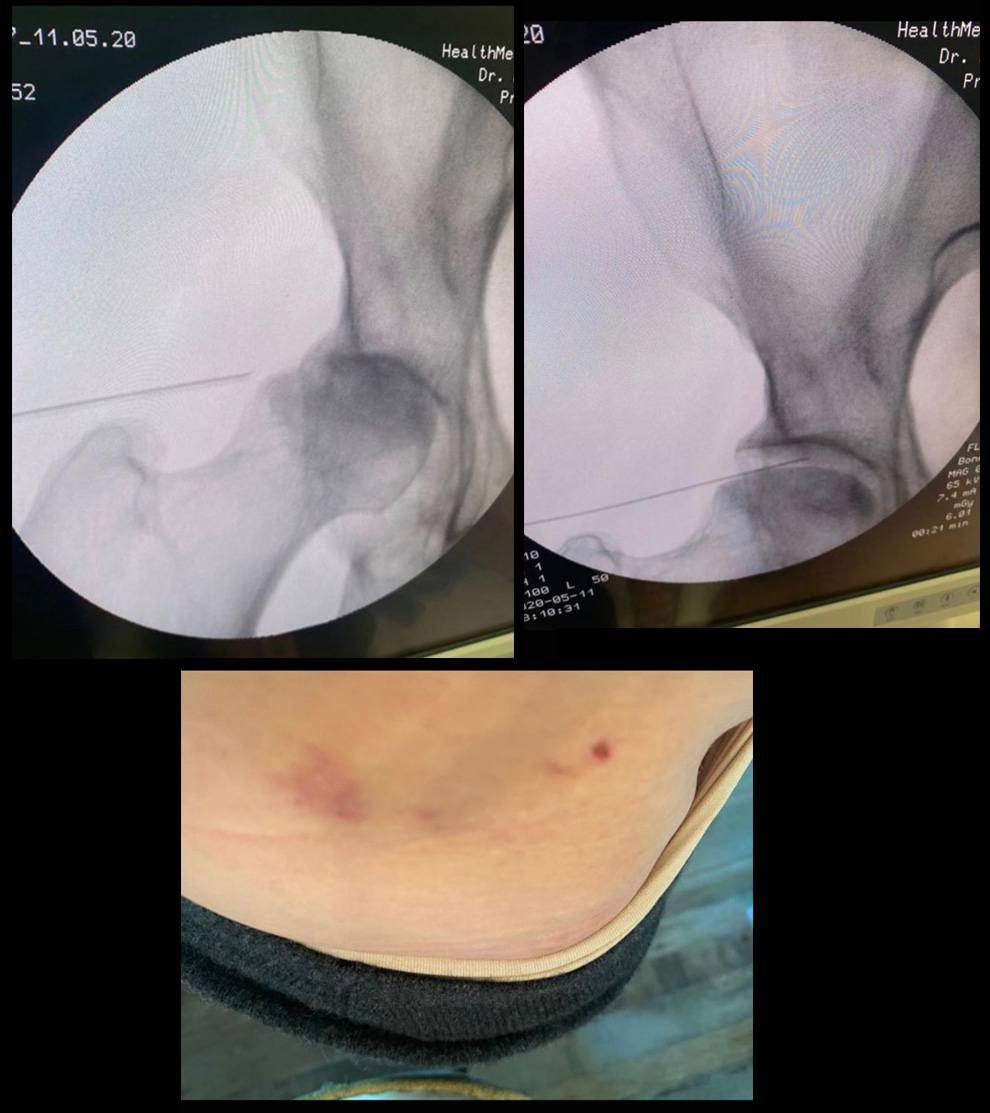

On y apprend également qu'à cette époque, une équipe française a mis au point un implant 3D composés de facteurs de croissance qui vont permettre la régénération de l’os et un hydrogel avec des cellules souches dérivées de la moelle osseuse du patient et qui va régénérer le cartilage. Cette intervention n'a donc rien d'anodin puisqu'elle nécessite un prélèvement de moelle osseuse. Les clichés du dos de Madonna et ses ecchymoses semblent confirmer qu'elle a bien subie cette intervention.